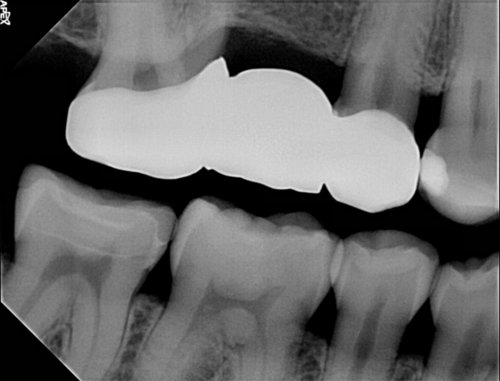

High Resolution CMOS Sensor

With the High Resolution CMOS chip you get crystal clear images in seconds. The Apex Dental Sensors capture high resolution images at 25 Theoretical line pairs per millimeter.